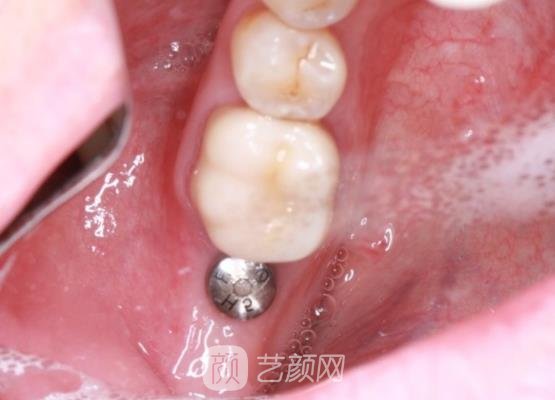

种植牙手术案例:

前几天开车的时候,因为走神所以出现了意外,造成我的牙齿有了缺失的情况,这对我的面部美观影响很大,所以我就一直想要做种植牙手术来改良我的牙齿问题。

可是因为我是第一次做牙齿方面的手术,不是很了解,害怕找到不正规的医院帮我进行手术,所以一直在选择医院的时候精心挑选,后来在网上看到了这家医院有着很多的好评,所以我就来到了这里。

刚到医院看到医院的整体环境是比较好的,布置整洁,卫生条件也比较高,让我比较满意,然后我就和医院医生进行了手术的预约处理,医生还主动的和我交流了一些关于种植牙手术方面的相关知识,让我对手术有了更多的了解。

之后医生又让我了解了一些手术的大概流程问题,然后又询问了我的身体情况,在确定我的身体没有一些特殊情况下,帮我拍了口腔全片,便按照我的牙齿大小帮我制定了几项适合我的手术方案供我选择。

方案确定好以后手术就开始了,医生先是给我的牙龈处进行了局部麻醉,麻醉的时候是有一些疼痛的感觉,但是随着时间的推移,麻醉剂有了成果,疼痛感觉也就基本上消失了,几个小时以后手术也就结束了。

结束手术的时候,我的牙龈处红肿的情况比较严重,有一些微微的肿胀,而且还有一些疼痛的感觉,医生告诉我这些情况比较正常,几天以后就会好了,让我不用太过于的担心。

然后医生又叮嘱了我一些关于术后的注意事项,告诉我当天不要进行口腔清洁,防止对牙龈处的伤口造成感染,延长手术的恢复期,饮食方面也不要吃一些比较坚硬的食物,防止种植牙松动然后脱落,当然粘性较大的食物也要尽量避免。

接下来的几个月,我一直按照医生的叮嘱,对待饮食问题都是很注意的,一直忌口,过程是真的很难熬的,但是为了我的牙齿问题,我还是坚持了下来。

现在我的种植牙已经恢复的很自自然了,真的就像是我自己的牙齿一样,而且口腔里边也没有一些异物的感觉,医生的医美技术还是比较厉害的,手术成果真的很好,让我很满意。